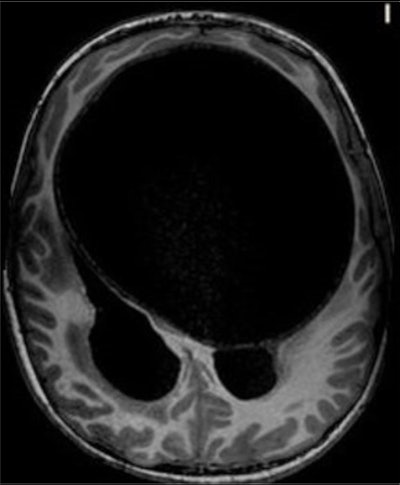

An axial T1-weighted MRI scan of a hydatid cyst. Clinical images courtesy of Dr. Carlos F. Ugas Chacape.